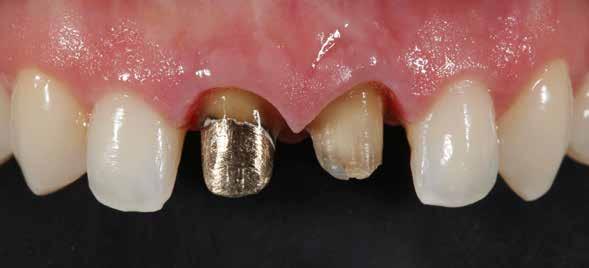

A mindennapi gyakorlatban gyakran találkozunk súlyos fogszuvasodással. A fogorvosnak mindig kihívást jelent a döntés, hogy kihúzzuk és implantátummal pótoljuk, vagy megmentjük a fogat, de kétséges a hosszú távú prognózis. Számos cikkből tudjuk, mint például Seltzer és Kim (Comparison of Long term survival of implant and endodontically treated teeth J Dent Res 93(1):19-26, 2014) cikke, hogy a fogak viszszanyerése jobb megoldás, különösen a fiatalabb betegeknél. A kirakós hiányzó kulcsa az általános fogorvos számára gyakran a maradó fogazat jó biomechanikai értékelése. Az endodontikusan kezelt fogak kudarcainak többsége valójában mechanikai hibákhoz, például repedéshez és töréshez kapcsolódik. A maradó fogszerkezet gondos biomechanikai értékelése, valamint a mechanikai teljesítményt javító technikákra való összpontosítás a legfontosabb a hosszú távú eredmény keresésében. A szerző praxisában a vertikális pre-

parálás és a minimális megközelítés kombinációja, valamint az ortodontikus extrúzió alkalmazása a restauratív fogászatban megváltoztatja a helyzetet, amint azt a következő eset is mutatja.

Az implantológia térhódítása után a restauratív/protetikai fogászatban a léc magasabbra került. A fogászati implantátumokkal való sikeresebb „versenyzéshez” a fogorvosoknak sokkal jobban kell összpontosítaniuk a fogak biomechanikai helyzetének értékelésére és javítására. A biomechanika mély megértése és a fogak teherbíró képességét javító technika alkalmazása a legfontosabb a hosszú távú siker érdekében.

Egy 35 éves kaukázusi férfi páciens az 1.4-es fog (felső első premoláris) törése miatt kereste fel rendelőnket, a törés ferde volt. A sérült fogak helyreállítása során az egyik legfontosabb lépés a megmaradt fogazat biomechanikai értékelése . Egy hiba ebben a fázisban káros a hosszú távú eredményre . A legtöbb repedést például a fogüregek helyreállító fogászathoz való helytelen előkészítése okozza. Ugyanígy a fennmaradó szerkezet helytelen értékelése idővel mechanikai okokból bekövetkező meghibásodáshoz vezethet.

2. ábra: Az okkluzális nézet a fogszerkezet mennyiségét mutatja, a röntgenfelvételen az 1.5. fogon II. osztályú szuvasodás is látható. Még ha lehetséges is ezeket az eseteket koronahosszabbítással kezelni, a végeredmény átlagosan nem kielégítő. A ferrule gyógyulása korlátozott, és olyan parodontális szövődményekkel is találkozunk, mint a fekete háromszögek, a szomszédos fogak gyökérkitettsége. A fogszabályozó extrúzió sokkal előnyösebb.

4. ábra: A fogszerkezet helyreállítása és a fogrestaurációs komplexum ellenálló képességének javítása érdekében ortodontikus extrúziót végeztek a szomszédos fogakra ragasztott drót és egy egyszerű rugalmas ligatúra segítségével.

10. ábra: A cirkónium-dioxid korona cementálása üveg-ionomer cementtel . Ezzel a megközelítéssel nyilvánvaló, hogy a ferrule menynyisége a szomszédos fogakra gyakorolt bármilyen komplikáció nélkül nyert. A parodontális apparátus valójában érintetlen. Nincsenek fekete háromszögek, nincs a szomszédos fogak gyökérkitettségének kockázata. Már a szülés napján megvan a papilla, amely kitölti az intraproximális tereket. A nyert ferrule mennyisége hatalmas. A bukkális falon könnyen felismerhetjük, hogy az egész fal már szilárd fogazati struktúrán van, a palatális falon pedig az ajánlott 1-1,5 mm-nél jóval több. A függőleges preparálással szintén könnyen meg tudjuk tartani a visszanyert fogszerkezet mennyiségét , különösen a pericervikális dentin területén, ami a legfontosabb a hosszú távú eredmény szempontjából.